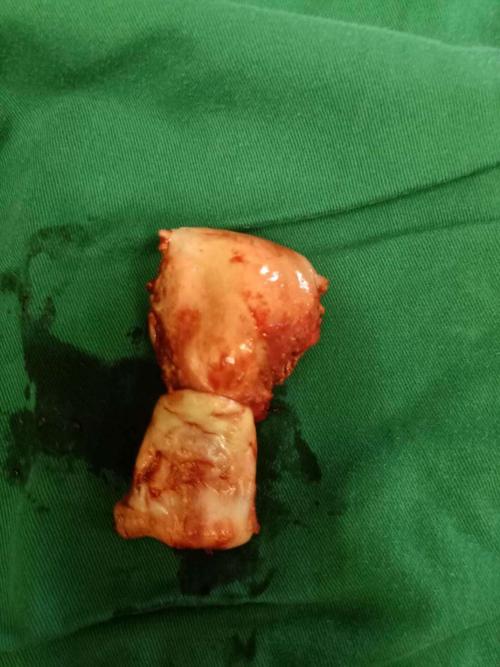

榆林一院病例分享-子宫脱垂行阴式全子宫切除术 阴道残端骶棘韧带悬吊

患者既往患有高血压病,心脏病;入院诊断:子宫脱垂3度,阴